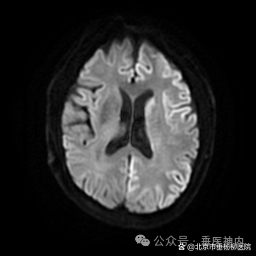

所有怀疑克-雅病诊断的患者,常规要进行脑脊液14-3-3蛋白检测;有条件的医疗机构,做脑脊液和(或)皮肤RT-QuIC检测。同时,血和脑脊液总tau蛋白、磷酸化tau蛋白/总tau蛋白比值有助于克-雅病的诊断及鉴别诊断。脑电图常出现特异性的周期性尖慢复合波。头核磁DWI相可见特异性地沿皮质沟回走行的带状和(或)双侧基底核区的异常高信号。

我科收治的两例患者脑电图一例是漫波背景,一例可见尖慢复合波,两例患者DWI影像均可见至少两个皮质区域沿皮质沟回走行的带状异常高信号,一例进行了脑脊液14-3-3蛋白检测,一例进行了血和脑脊液总tau蛋白、磷酸化tau蛋白/总tau蛋白比值检测,结果均高度提示患者为克-雅病可能性大。

典型头核磁结果: